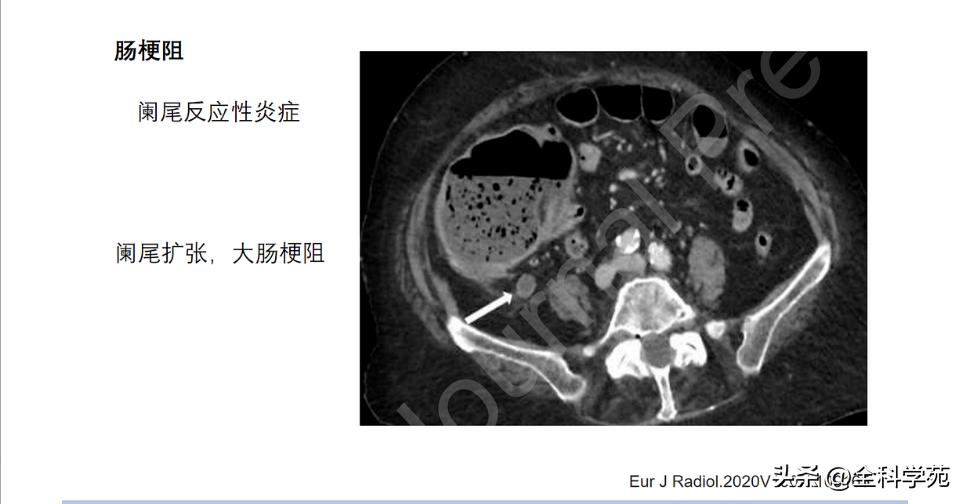

并发症( complications)

◆ 小肠梗阻 (Small bowel obstruction)